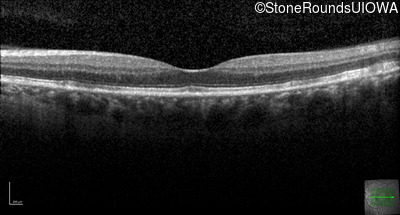

Late Onset Retinal Dystrophy (IIIA3)

Age at visit: 61 years

This 61 year old woman reports some moderate night blindness over the past 10 years.

Diagnosis & molecular findings

Late Onset Retinal Dystrophy C1QTNF5 Ser163Arg AGC>AGA   AD